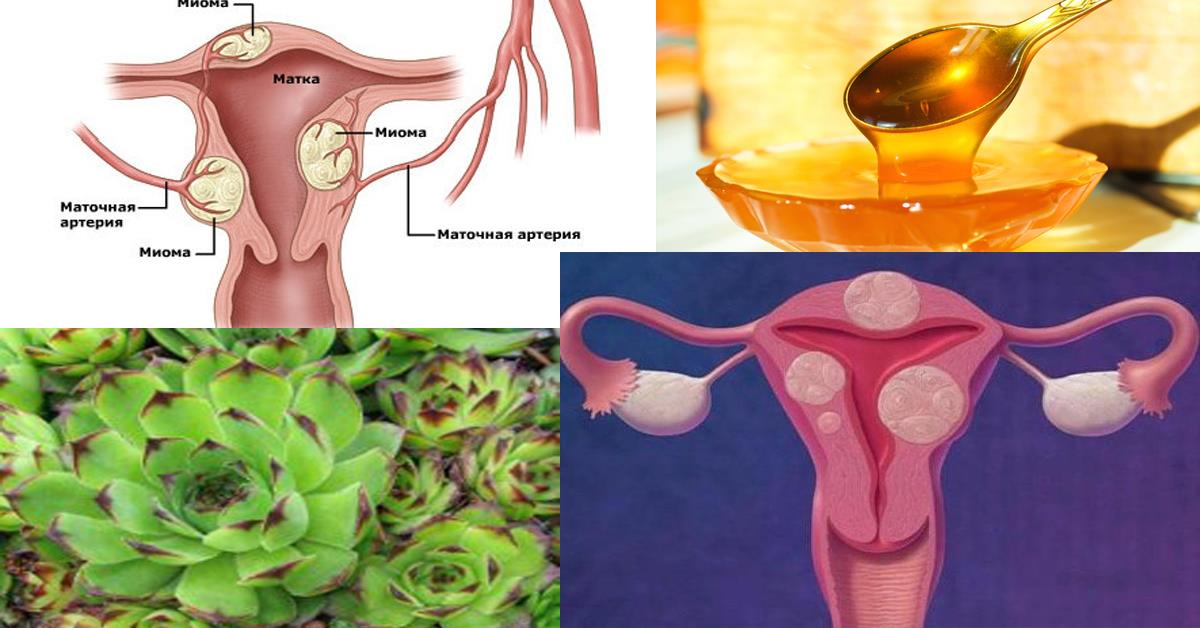

Анатомия женского организма: строение и функции матки

Раздел: Фотопуть к знанию